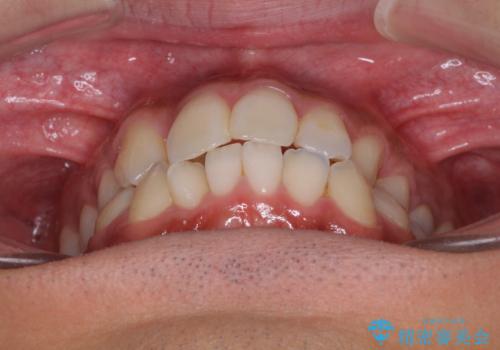

【モニター】左右のクロスバイトをインビザラインできれいに改善

- 前歯のデコボコとクロスバイトを気にして来院された患者様です。

下顎の歯列弓に対して上顎歯列弓がやや小さく、側方の歯を中心にクロスバイトが見受けられました。

クロスバイトの改善は、インビザラインの場合歯髄壊死のリスクや咬み合わせが改善しきらないリスクがあるため、ワイヤー矯正をお勧めすることが多いですが、患者様の希望によりインビザラインにて矯正治療を行うこととしました。

後方に隠れていた上顎前歯は矮小歯であるため、矯正治療の途中でオールセラミッククラウンを装着し、左右対称の大きさでの仕上がりを目指すこととしました。